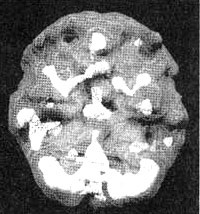

Мозг Роба. Результаты сканирования SPECT

Трехмерное изображение — активный мозг, вид сверху.

До лечения: обратите внимание на выраженное усиление активности в поясной системе (см. стрелку).

После лечение Anafranil. Активность поясной системы нормализовалась.

Трехмерное изображение — активный мозг, вид сбоку.

После трех лет неуклонного улучшения состояния на фоне приема Anafranil (оба раза, когда предпринимались попытки снизить дозу, симптомы возвращались), повторное сканирование показало нормализацию функции мозга.